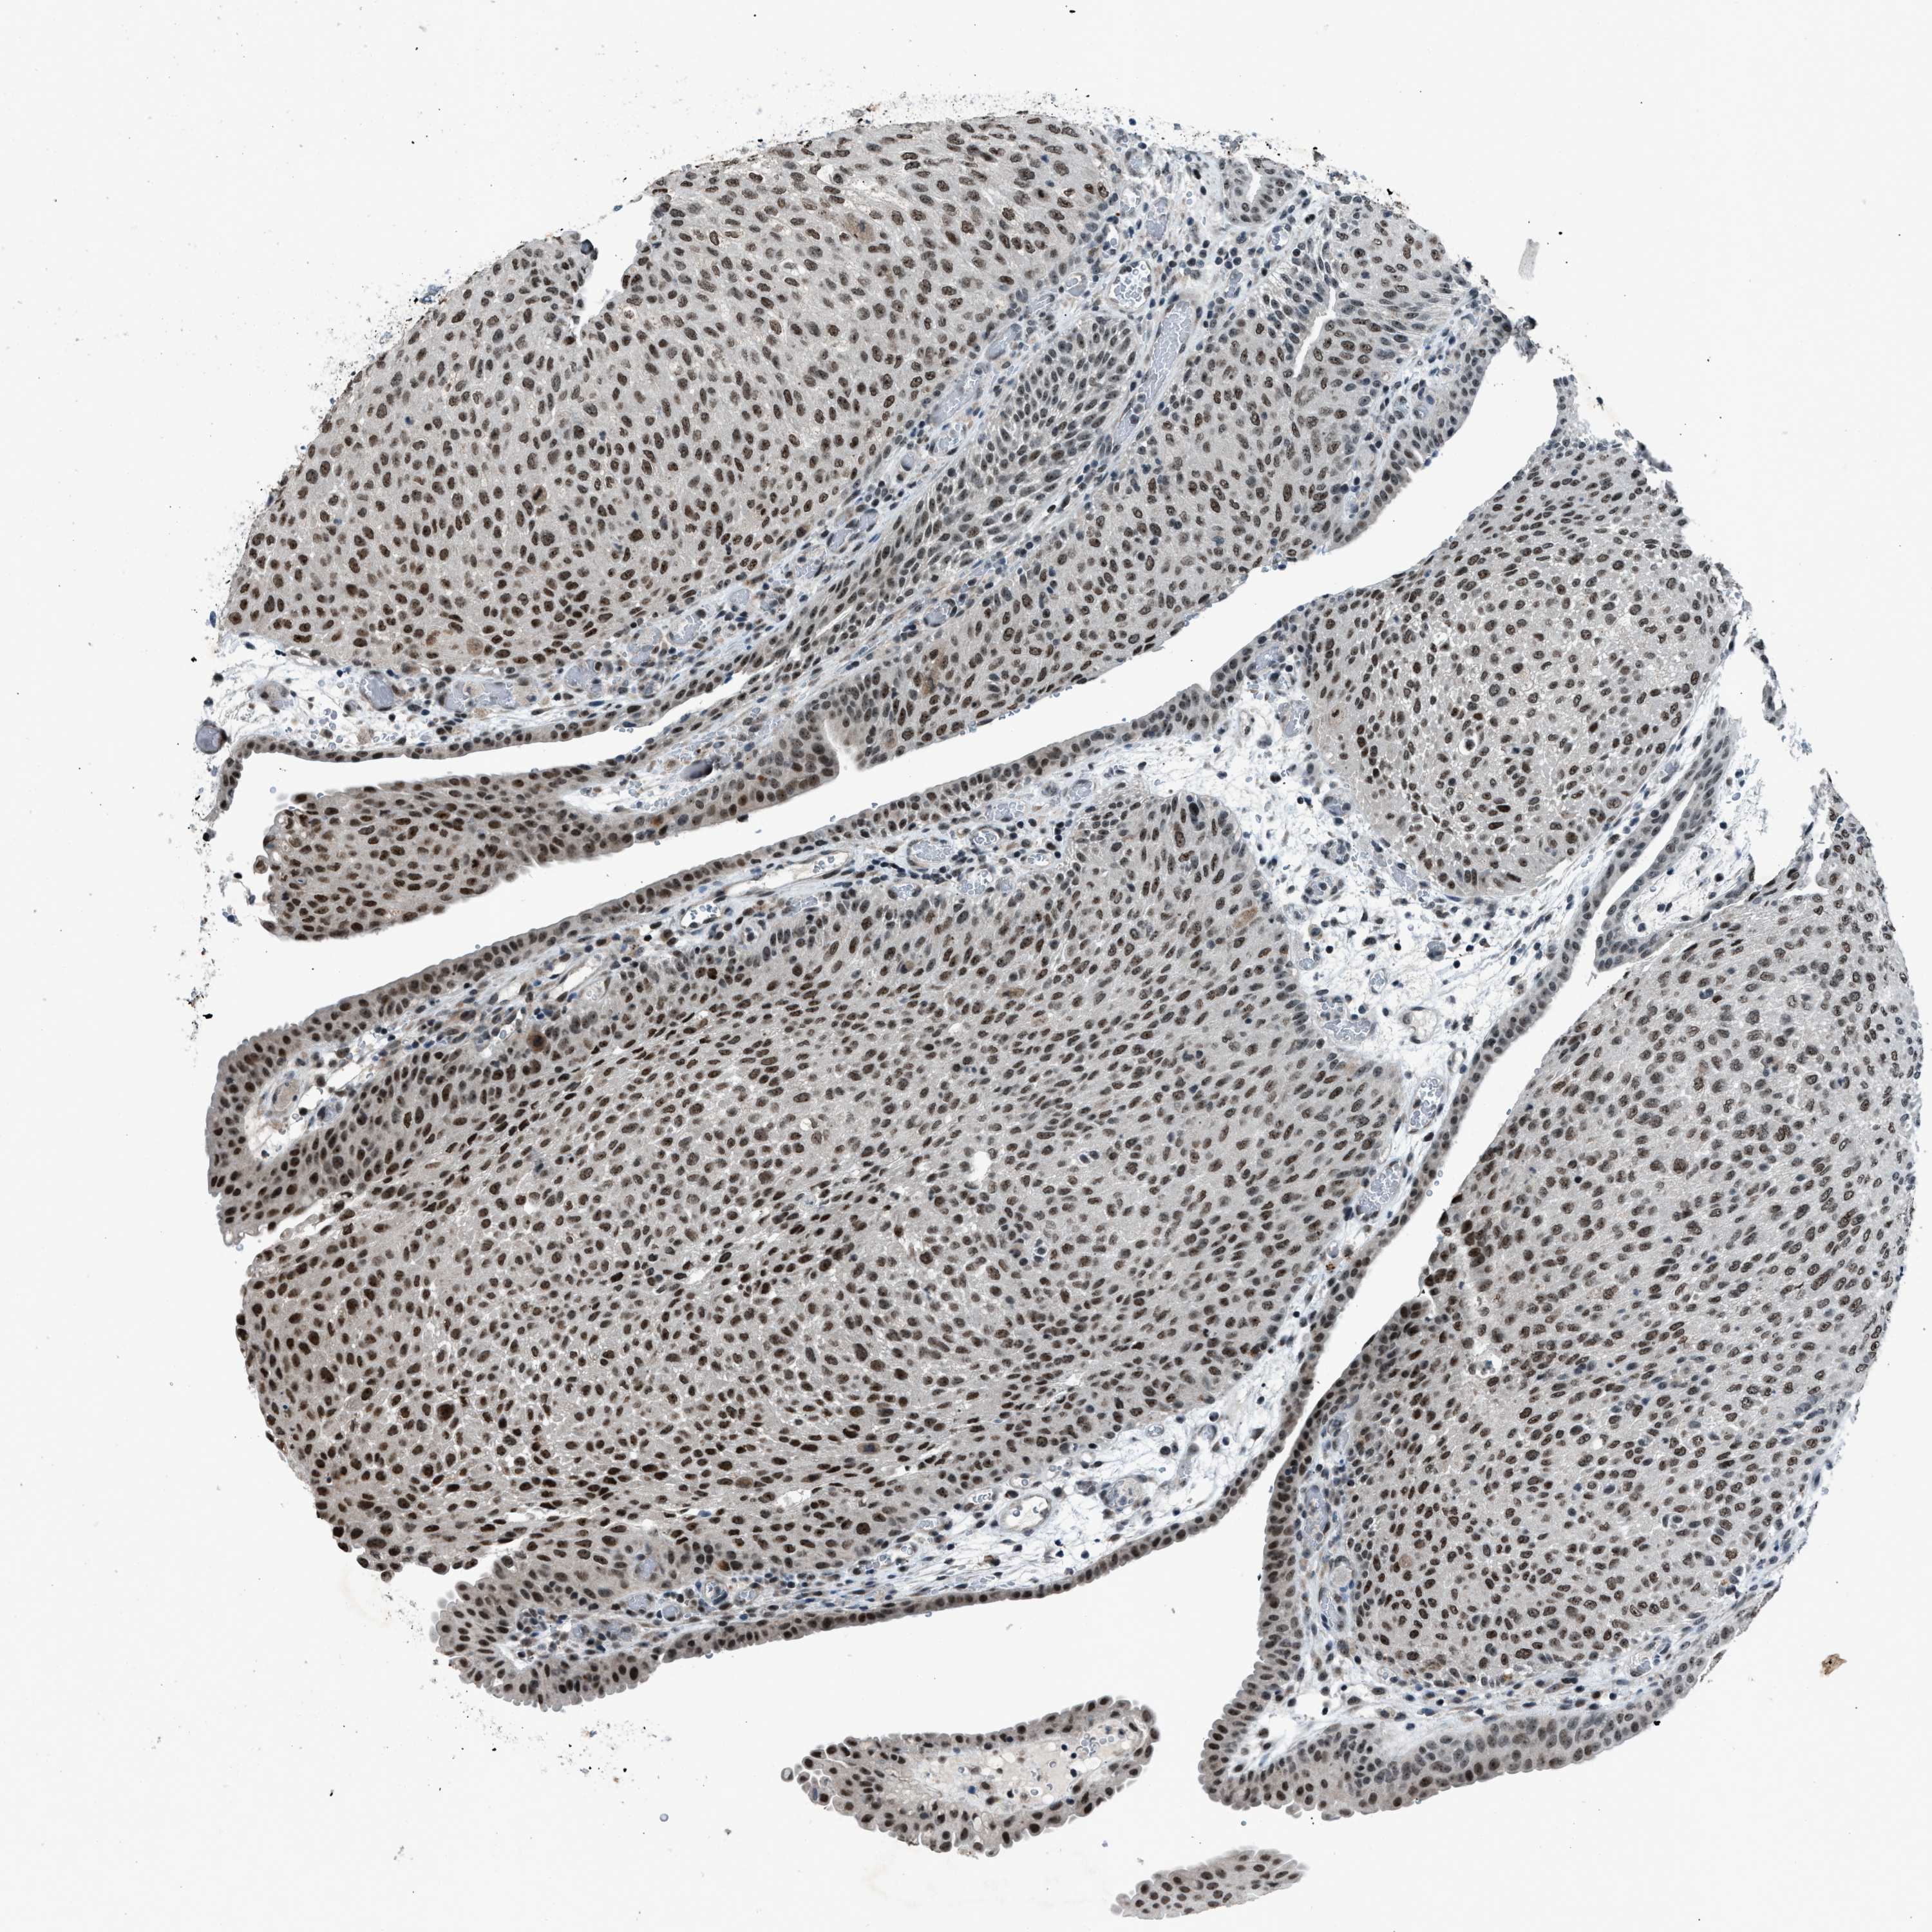

UROTHELIAL CANCER - Protein expressioni

A mouse-over function shows sample information and annotation data. Click on an image to view it in a full screen mode. Samples can be filtered based on level of antibody staining by selecting one or several of the following categories: high, medium, low and not detected. The assay and annotation is described here.

Note that samples used for immunohistochemistry by the Human Protein Atlas do not correspond to samples in the TCGA dataset.

Antibody stainingi

Antibody staining in the annotated cell types in the current human tissue is reported as not detected, low, medium, or high, based on conventional immunohistochemistry profiling in selected tissues. This score is based on the combination of the staining intensity and fraction of stained cells.

Each image is clickable and will lead to virtual microscopy that enables deeper exploration of all samples and also displays staining intensity scores, fraction scores and subcellular localization as well as patient and tissue information for each sample.

Antibody CAB018364

Staining

High

Medium

Low

Not detected

Intensity

Strong

Moderate

Weak

Negative

Quantity

>75%

75%-25%

<25%

None

Location

Nuclear

Cytoplasmic/membranous

Cytoplasmic/membranous,nuclear

Urothelial carcinoma, Low grade

Urothelial carcinoma, High grade